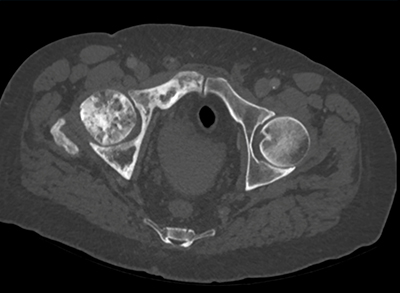

The best diagnosis in this patient with abdominal pain is?

metastatic prostate cancer

lymphoma

Pagets disease

metastatic breast cancer